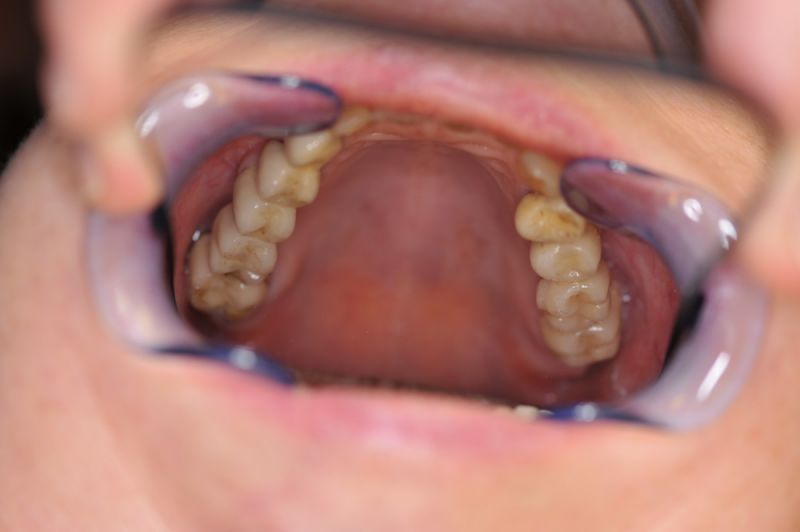

Es war eine Kombination aus Schmerzen bis an die Suizidgrenze, beschränkten wirtschaftlichen Möglichkeiten, sehr stark eingeschränkten Möglichkeiten der für Implantate zur Verfügung stehenden Knochenverhältnisse in einem stark atrophierten Unterkieferseitenzahnbereich und zudem dann auch noch durch auftretenden Problemen bei der Implantatinsertion und nachfolgenden Versorgung der Implantate.

Alle 3 Monate Recall! Das ist jetzt Pflicht für diese Patientin und zwar so lange, so lange sie mit dieser Arbeit durch die Gegend laufen möchte! Und eiserne Disziplin bei der Mundhygiene!

Die Problematik der Implantatversorgungen kann man in einer Analogie folgendermaßen darstellen. Die räumlich beengten Zustände gleichen dem Tanz eines Paares auf einer Briefmarke, und der gleichzeitigen Schritt- und Fusshaltung, dass beim Tanzen die Schuhe geputzt werden können!